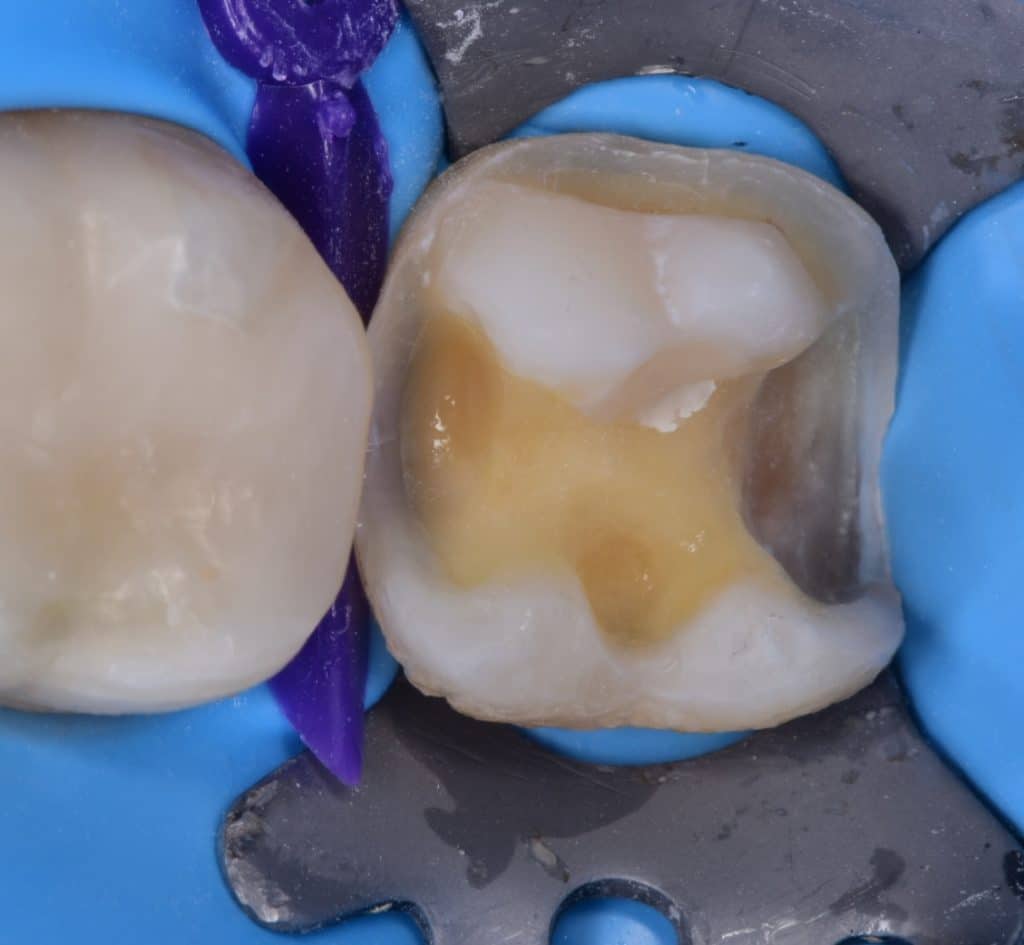

Saddle metal band

IDS with G2 bond

RC with flowable composite from GC, ever x flow for dentim replacement